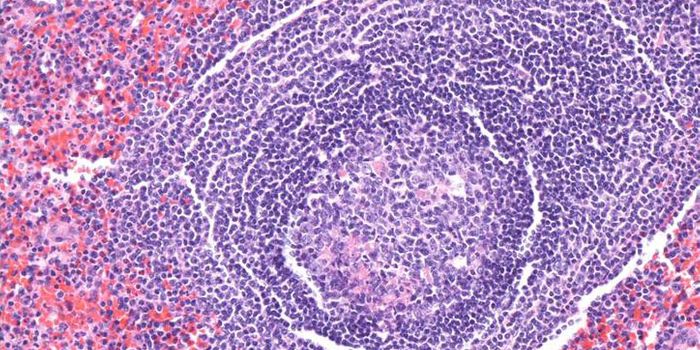

MAR 18, 2015Immunology

After a chance observation in the lab, researchers found a method that can force dangerous leukemia cells in the l ... -

MAY 11, 2016ImmunologyB cells, which are mostly known for antibody production in the face of invading pathogens, provide another function in t ...

-